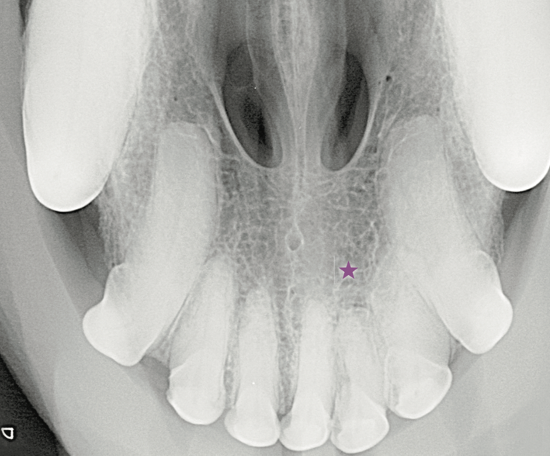

Wann ist eine Extraktion überzähliger Zähne notwendig? Das Röntgenbild kann Aufschluss geben, wie in diesem Fall bei einem Mischlingshund, 8 Jahre, männlich kastriert.

Der Röntgenbefund zeigt den doppelt angelegten I2 im Oberkiefer links sowie eine periapikale Radioluzenz (★) und einen erweiterten Parodontalspalt (▶️). Aufgrund der Überlagerung der Wurzelbereiche wie hier im linken Incisivibereich konnte dieser erst durch die Anfertigung einer intraoralen Schrägaufnahme besser beurteilt werden.

Differentialdiagnostisch sollten persistierende Incisivi – Milchzähne (▶️) ausgeschlossen werden. Sofern stomatologisch wie röntgenologisch keine Hinweise auf eine Zahnerkrankung vorliegen, kann der zusätzliche Zahn belassen werden. Allerdings wird ein Zuchtausschluss empfohlen.

Das Röntgenbild kann Aufschluss geben, wie in diesem Fall bei einem Mischlingshund, 8 Jahre, männlich kastriert."